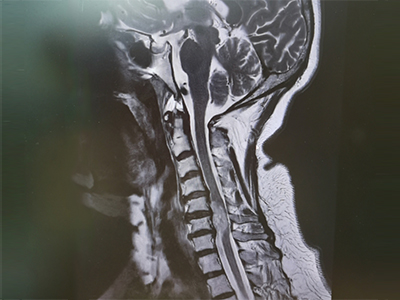

脊柱脊髓神经微创中心以微创技术为引领,以功能恢复为目标,主要治疗脊柱外伤、肿瘤、退行性病变、脊柱畸形等疾病。团队利用神经外科显微技术,结合神经内镜微创技术,对脊柱间盘变性疾病、颈腰椎管狭窄、颈腰椎间孔狭窄、颈腰椎间盘突出、颈腰椎体不稳、脊柱骨折、寰枢椎脱位、脊柱肿瘤、椎管内肿瘤、脊髓损伤、脊髓空洞、脊髓栓系等疾病进行高效、特色手术治疗,如颅颈交界区畸形寰枕减压内固定术、脊柱肿瘤全脊椎切除内固定术、微创椎管内肿瘤切除术、微创脊柱旁肿瘤切除术、寰枢椎脱位椎间融合内固定术、脊柱骨折微创经皮椎弓根钉内固定术、经椎间孔椎间融合内固定术(MIS—TLIF)等,最大程度降低脊柱脊髓手术创伤,具有创伤小、输血少、恢复快、口碑好,出院早等优势。

• 颈椎间盘切除、椎管减压术 6